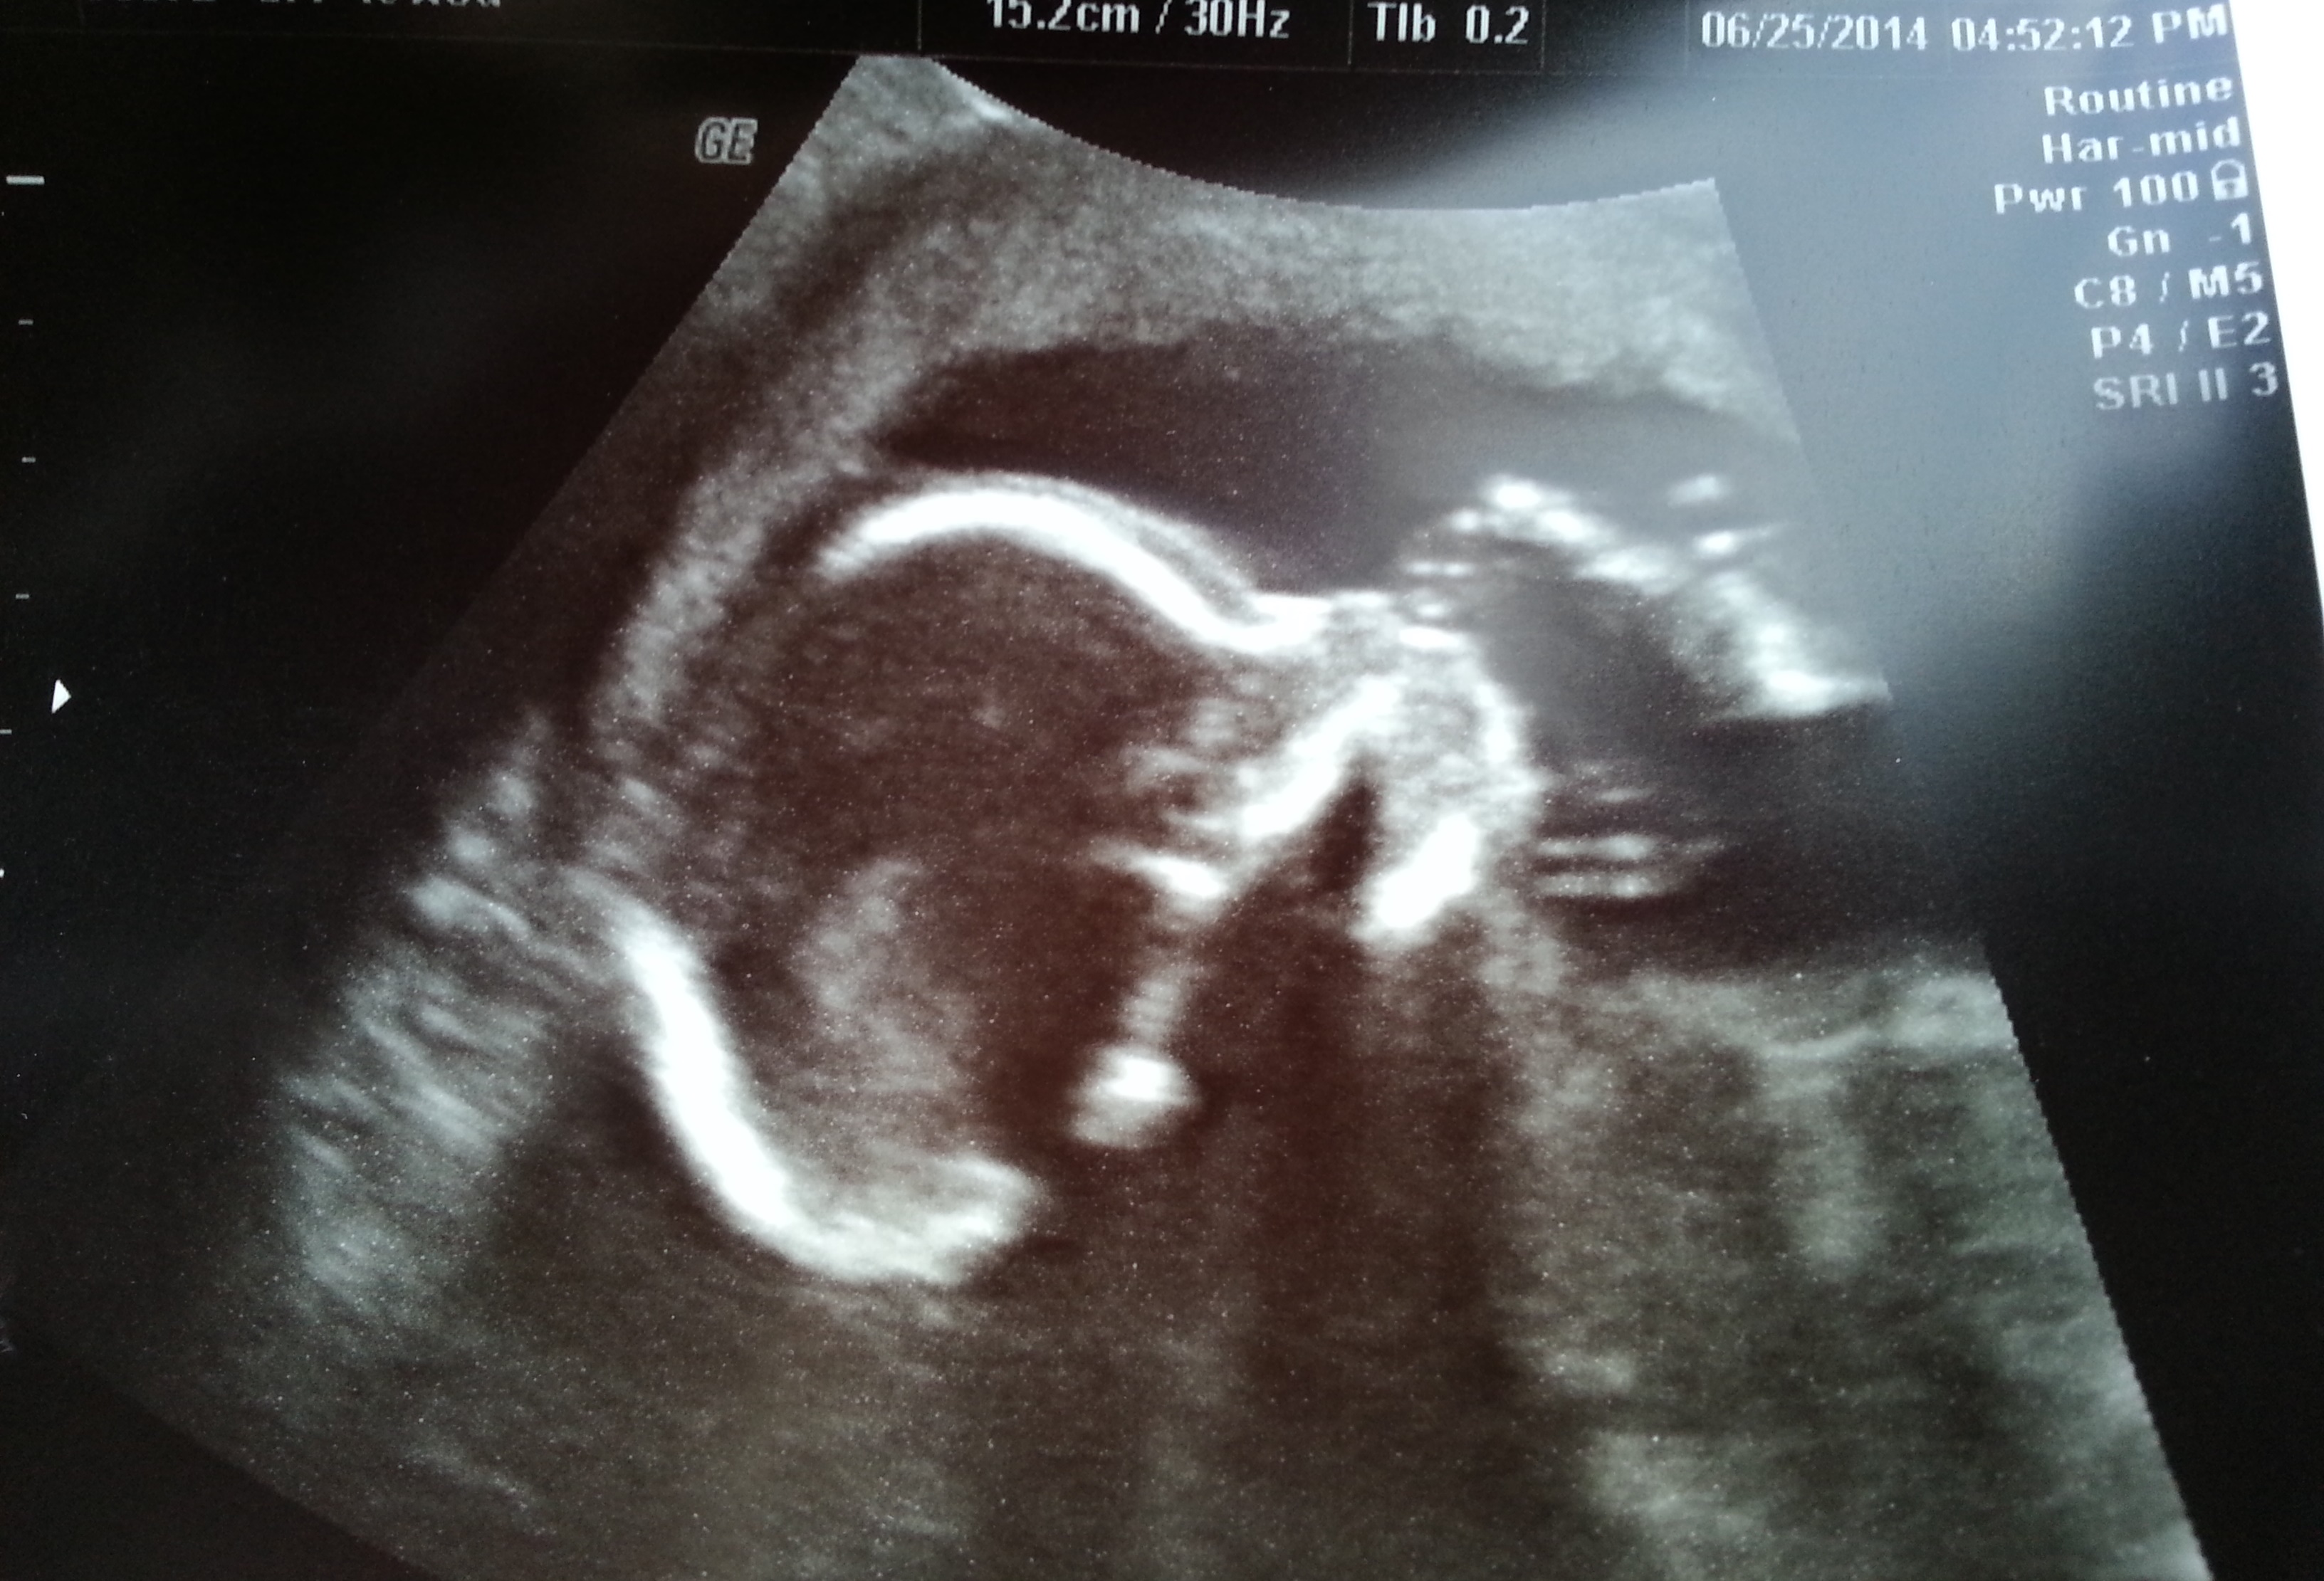

YAY...I finally get to post my A/S.  We were strong and stayed Team Green even though I caught DH every once in awhile trying to cheat but he had no clue what he was looking at haha.  Baby looks great, happy & healthy.  I totally forgot to ask what the HB was but does weigh 10 ozs..  Only little thing was that right now LO is breech but we have plenty of time for that to change.  LO was very cooperative so she was able to go pretty fast until she got to the feet lol then there was some poking and proding lol.  It was so great to see the little munchkin again.  I go for one more scan around 35/36 wk area.

I tried to shrink the pics...Hope they aren't too big.